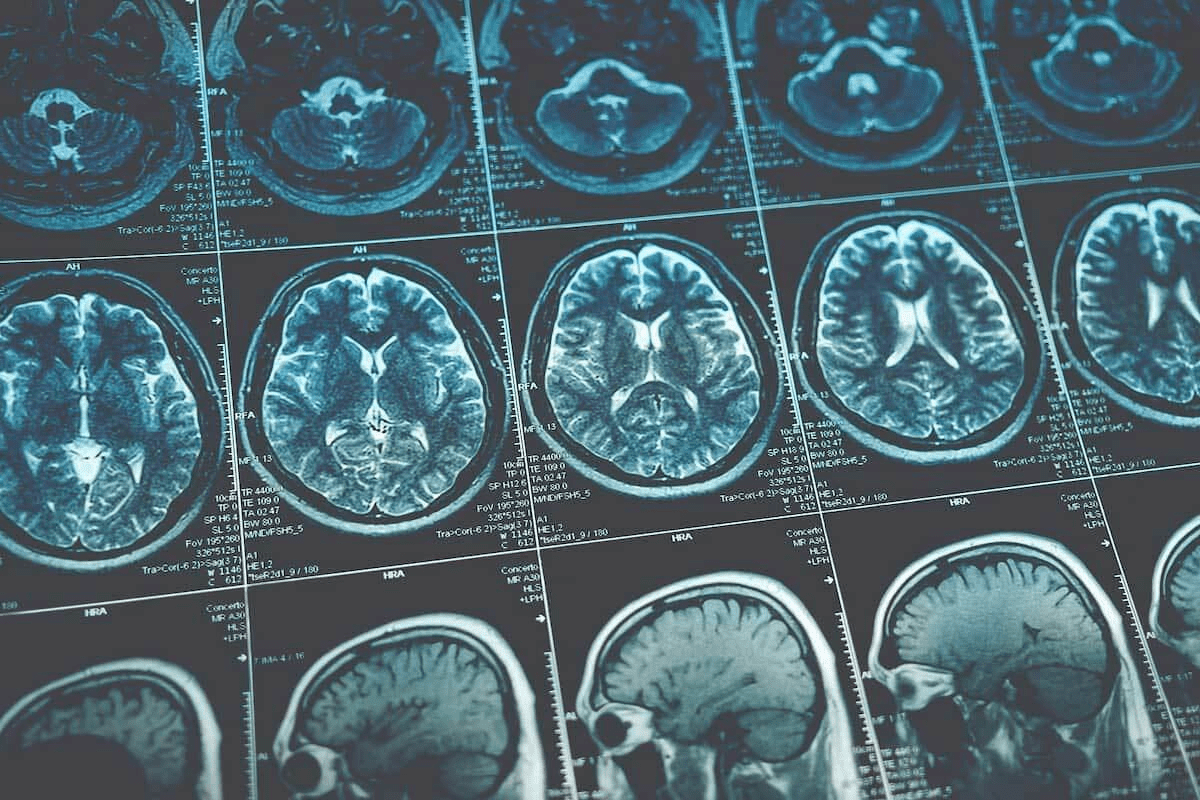

Imaging Studies and Other Assessments

Imaging studies and other tests are also used to keep an eye on patients. These include bone scans, CT scans, or MRI. They help find any cancer that might have spread or come back.

Doctors decide on these tests based on PSA levels, symptoms, and overall health. By using PSA tests and imaging, doctors get a full picture of the patient’s health. This helps them make the best care plans.